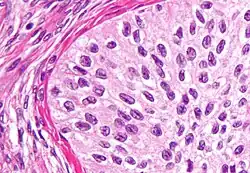

High magnification micrograph of a Brenner tumor, a type of surface epithelial-stromal tumor. H&E stain.

Brenner tumour. H&E stain.

Brenner tumors are uncommon surface-epithelial stromal cell tumors in which the epithelial cell (which defines these tumors) is a transitional cell. These are similar in appearance to bladder epithelia. The tumors may be very small to very large, and may be solid or cystic. Histologically, the tumor consists of nests of the aforementioned transitional cells within surrounding tissue that resembles normal ovary. Brenner tumors may be benign or malignant, depending on whether the tumor cells invade the surrounding tissue.